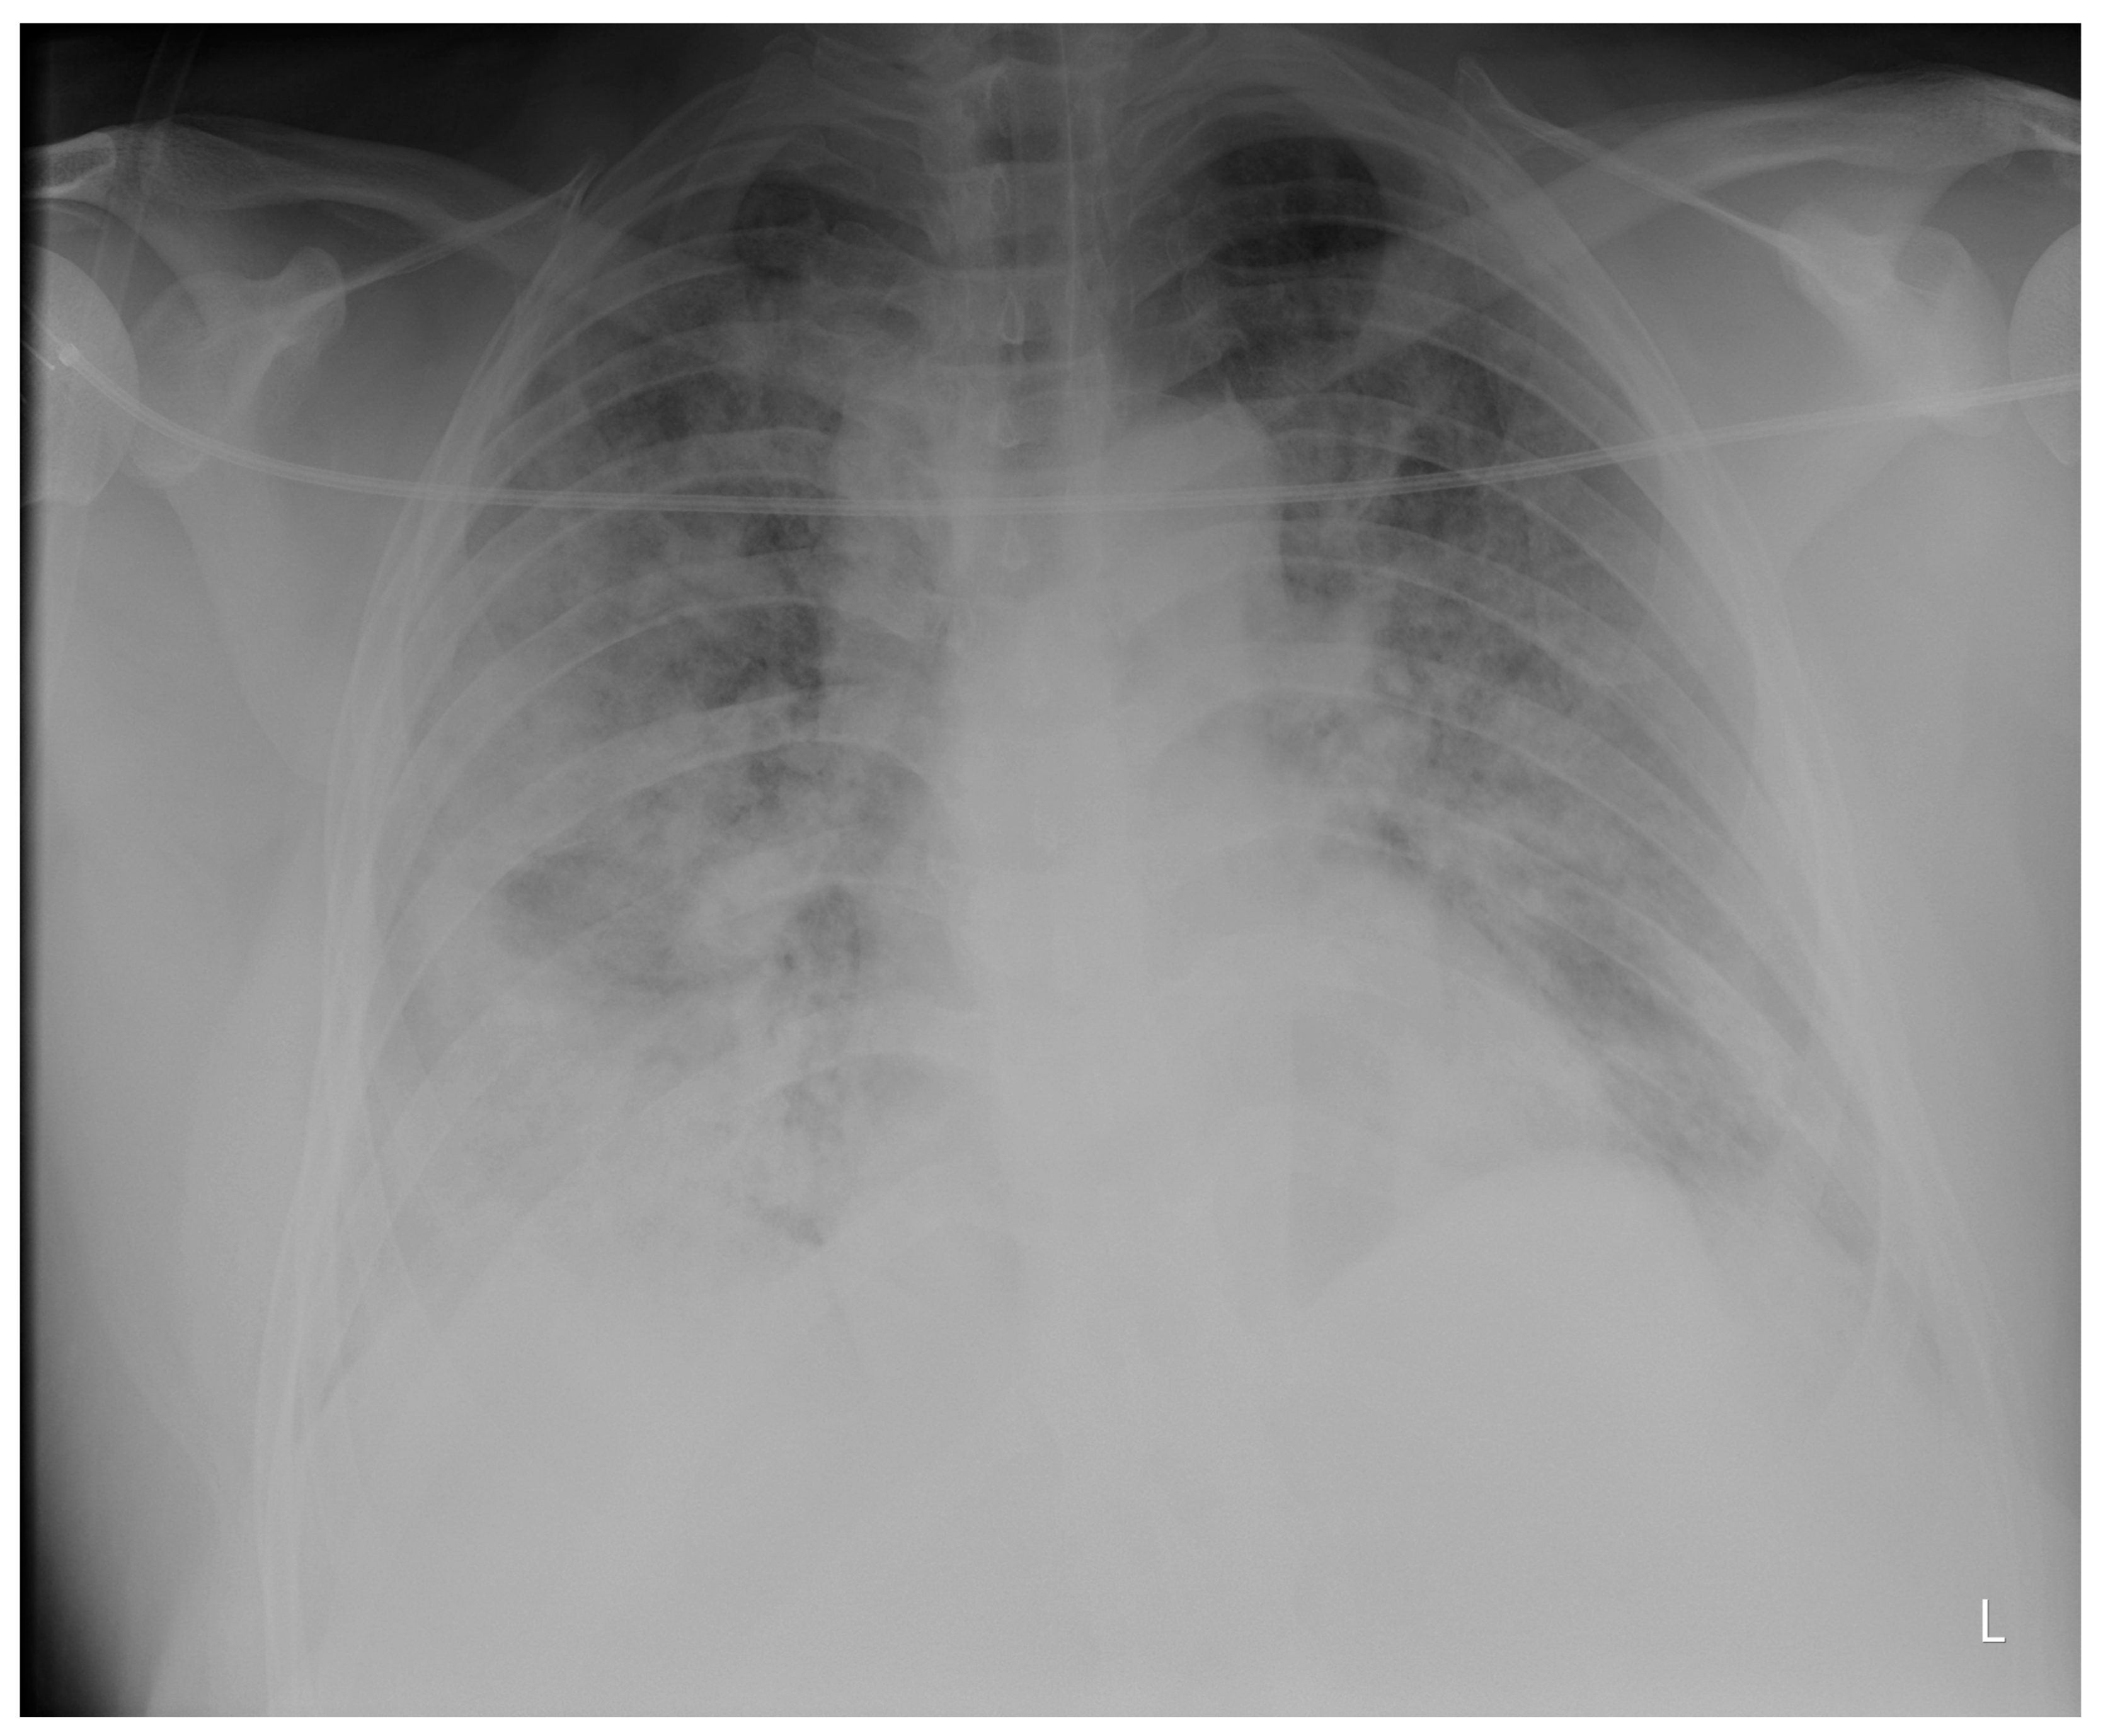

Laboratory findings were mostly normal; C-reactive protein was elevated in all patients with a mean value of 129.7 ± 80.74 mg/L. The arterial blood gas analysis showed hypoxemic respiratory failure. Chest X-rays in all patients showed bilateral inhomogeneous infiltrates (Figure 1 and Figure 2). In three patients, CTPA was performed, which ruled out pulmonary thromboembolism, but ground-glass opacifications with consolidation of the lung parenchyma were described in all of them (Figure 3 and Figure 4) [15].

Figure 3. CTPA upon admittance: patient 1. Bilateral ground glass opacifications (severity score: 15–25; chest CT severity score: 14) typical for COVID-19 pneumonia.